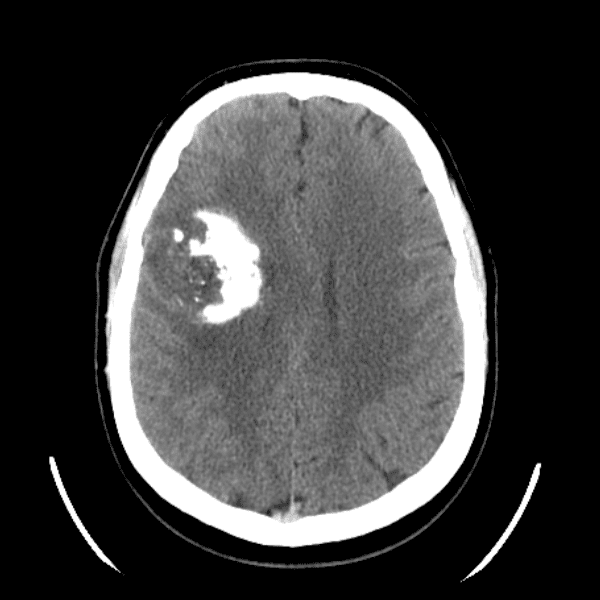

Classic Cases